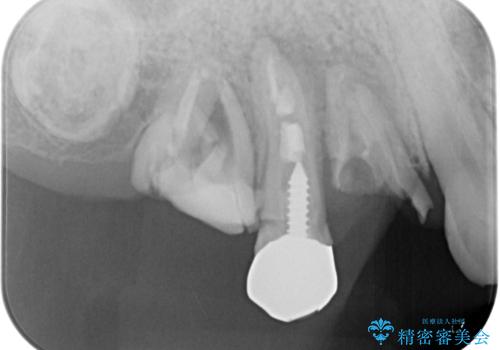

臼歯はもはや咬み合わせに寄与していない状態であり、3歯を抜去してインプラント2本埋入によるブリッジ補綴を計画しました。

セオリーとしては、インプラント補綴治療により奥歯の咬み合わせを確立してから、前歯部の処置を行うことになりますが、初めてのインプラント治療であることや、前歯部の見た目が気になっていることから、前歯の抜歯即時埋入インプラントによる補綴治療を先行して行い、並行して奥歯のインプラント治療を進めて行くこととしました。